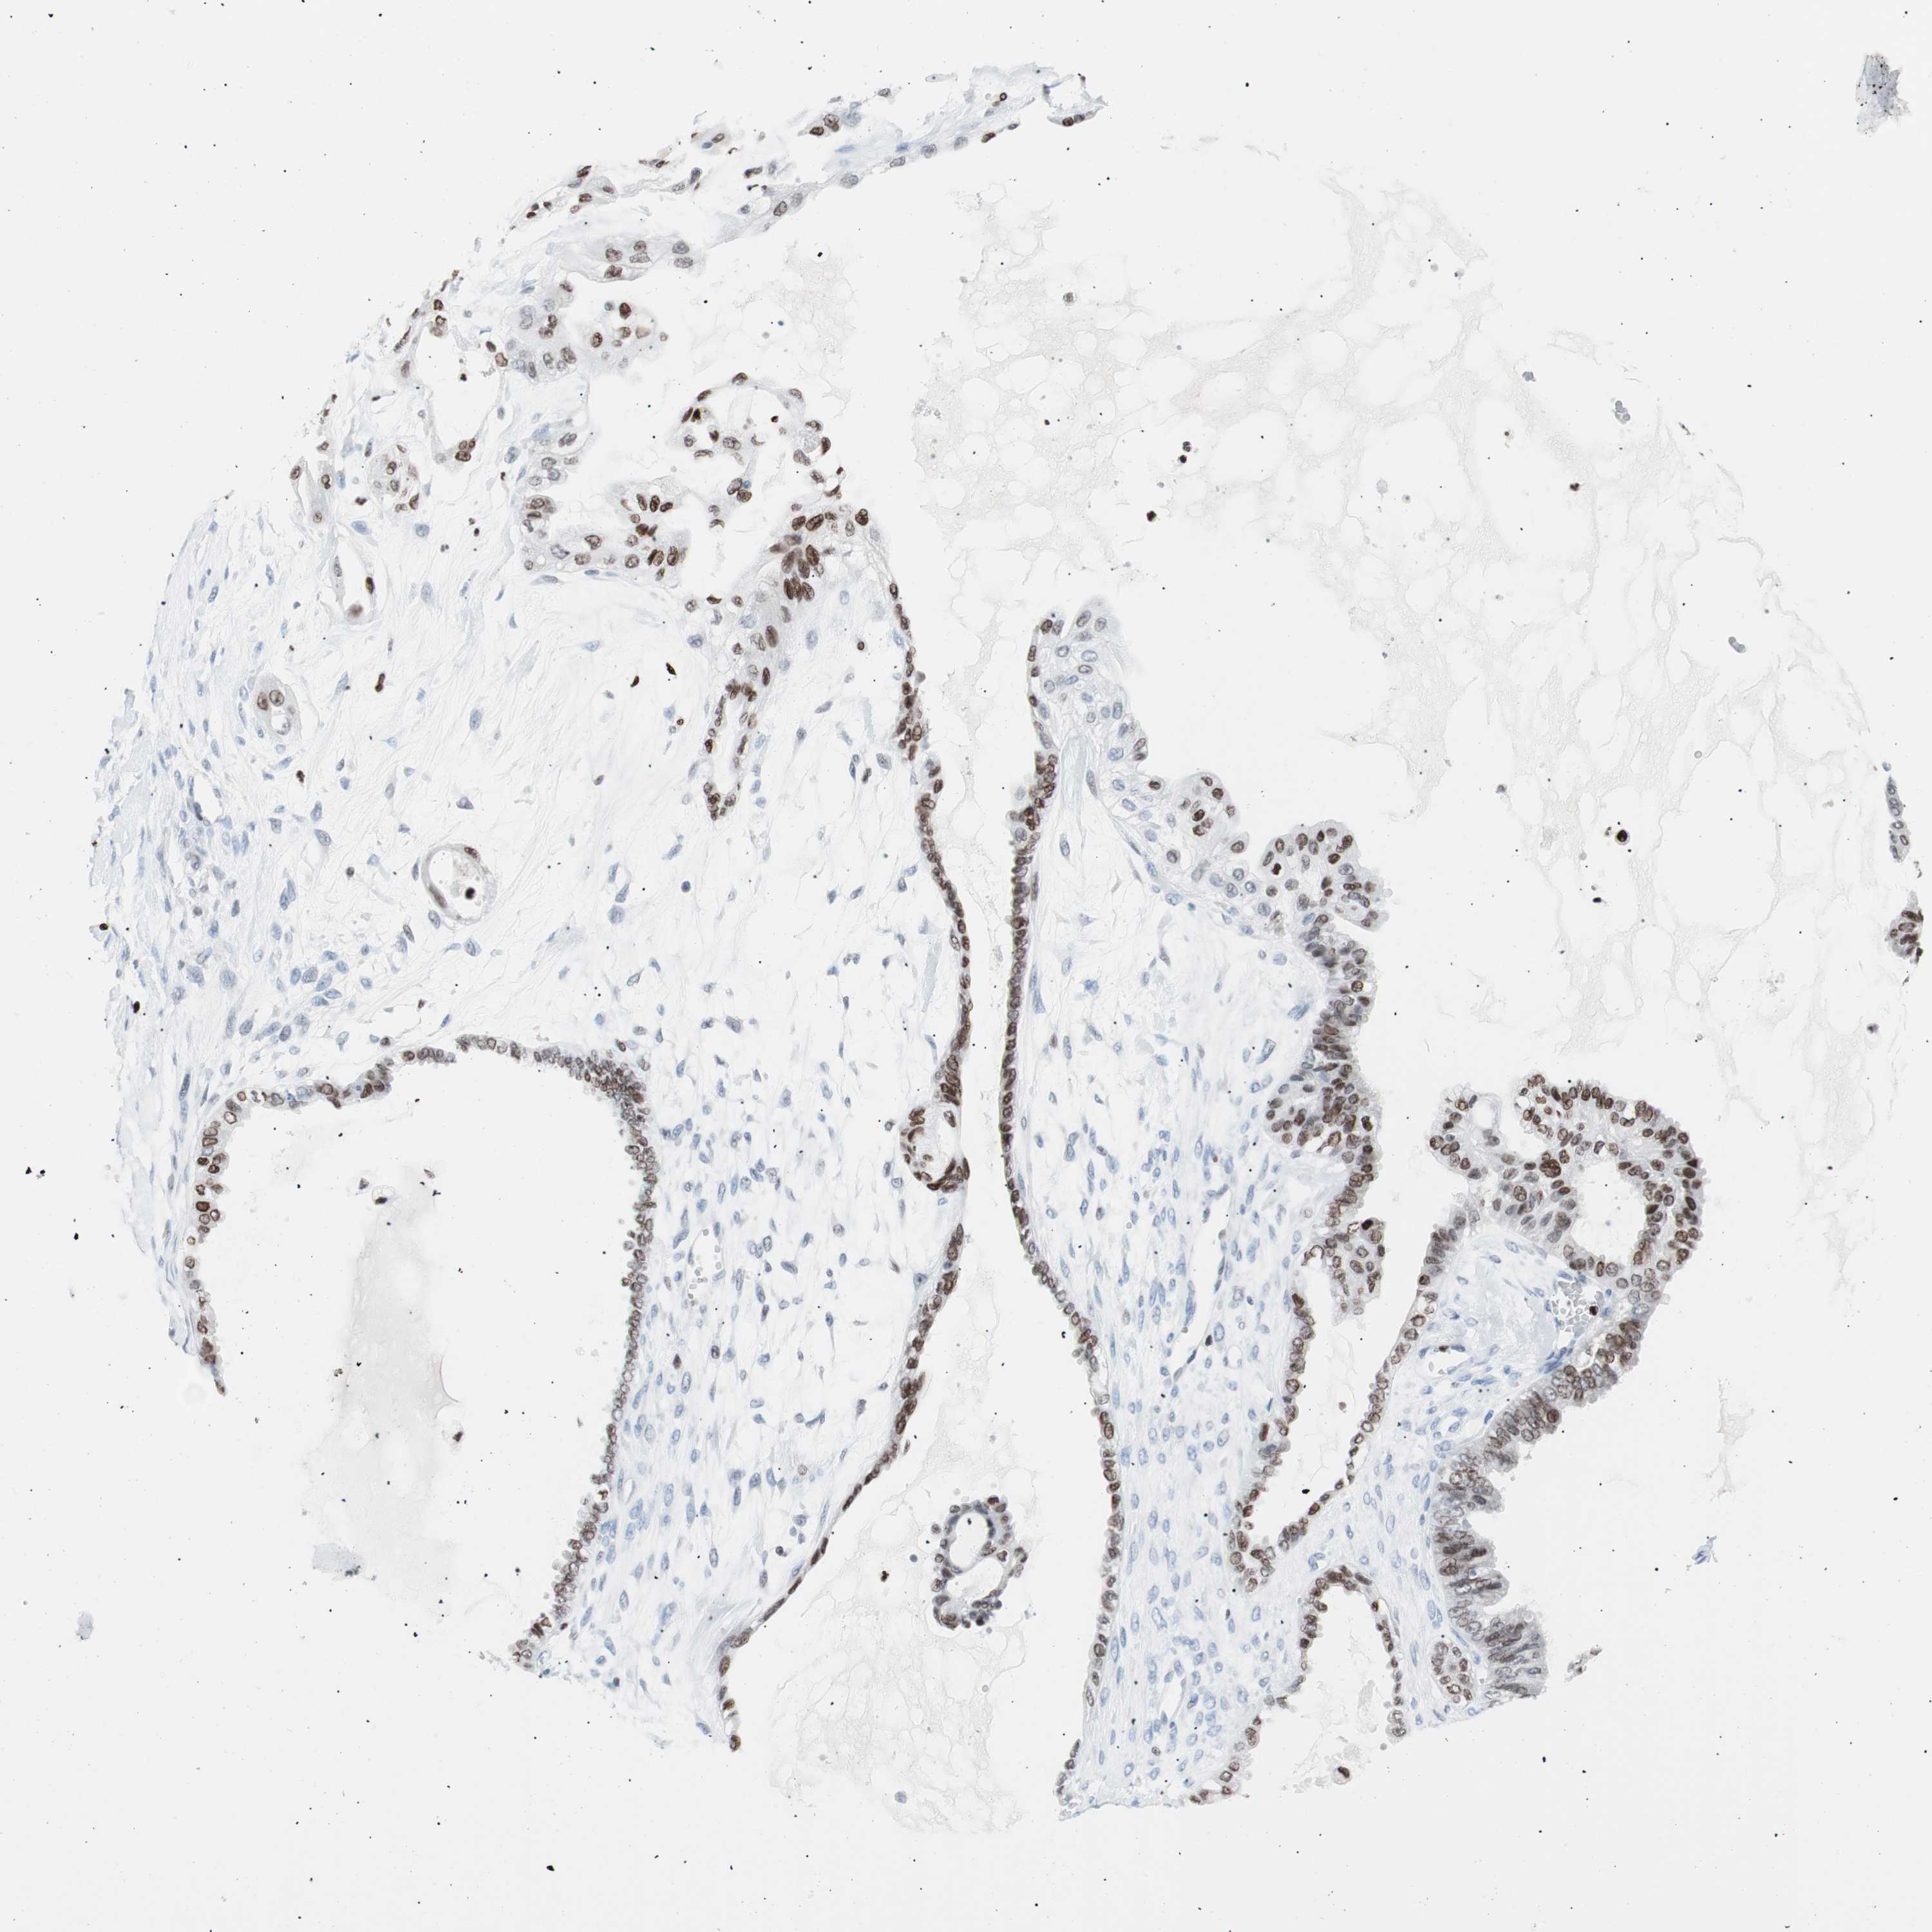

OVARIAN CANCER - Protein expressioni

A mouse-over function shows sample information and annotation data. Click on an image to view it in a full screen mode. Samples can be filtered based on level of antibody staining by selecting one or several of the following categories: high, medium, low and not detected. The assay and annotation is described here.

Note that samples used for immunohistochemistry by the Human Protein Atlas do not correspond to samples in the TCGA dataset.

Antibody stainingi

Antibody staining in the annotated cell types in the current human tissue is reported as not detected, low, medium, or high, based on conventional immunohistochemistry profiling in selected tissues. This score is based on the combination of the staining intensity and fraction of stained cells.

Each image is clickable and will lead to virtual microscopy that enables deeper exploration of all samples and also displays staining intensity scores, fraction scores and subcellular localization as well as patient and tissue information for each sample.

Antibody CAB004213

Staining

High

Medium

Low

Not detected

Intensity

Strong

Moderate

Weak

Negative

Quantity

>75%

75%-25%

<25%

None

Location

Nuclear

Cytoplasmic/membranous

Cytoplasmic/membranous,nuclear

Cystadenocarcinoma, serous, NOS

Carcinoma, endometroid

Carcinoma, NOS

Cystadenocarcinoma, mucinous, NOS